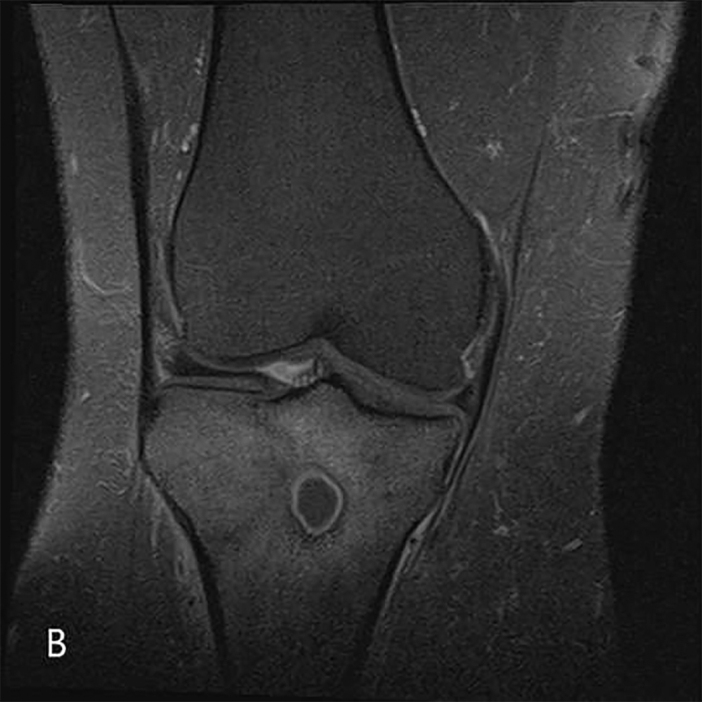

Fig. 1B.

T1 post contrast fat saturation image shows enhancement of the granulation tissue.